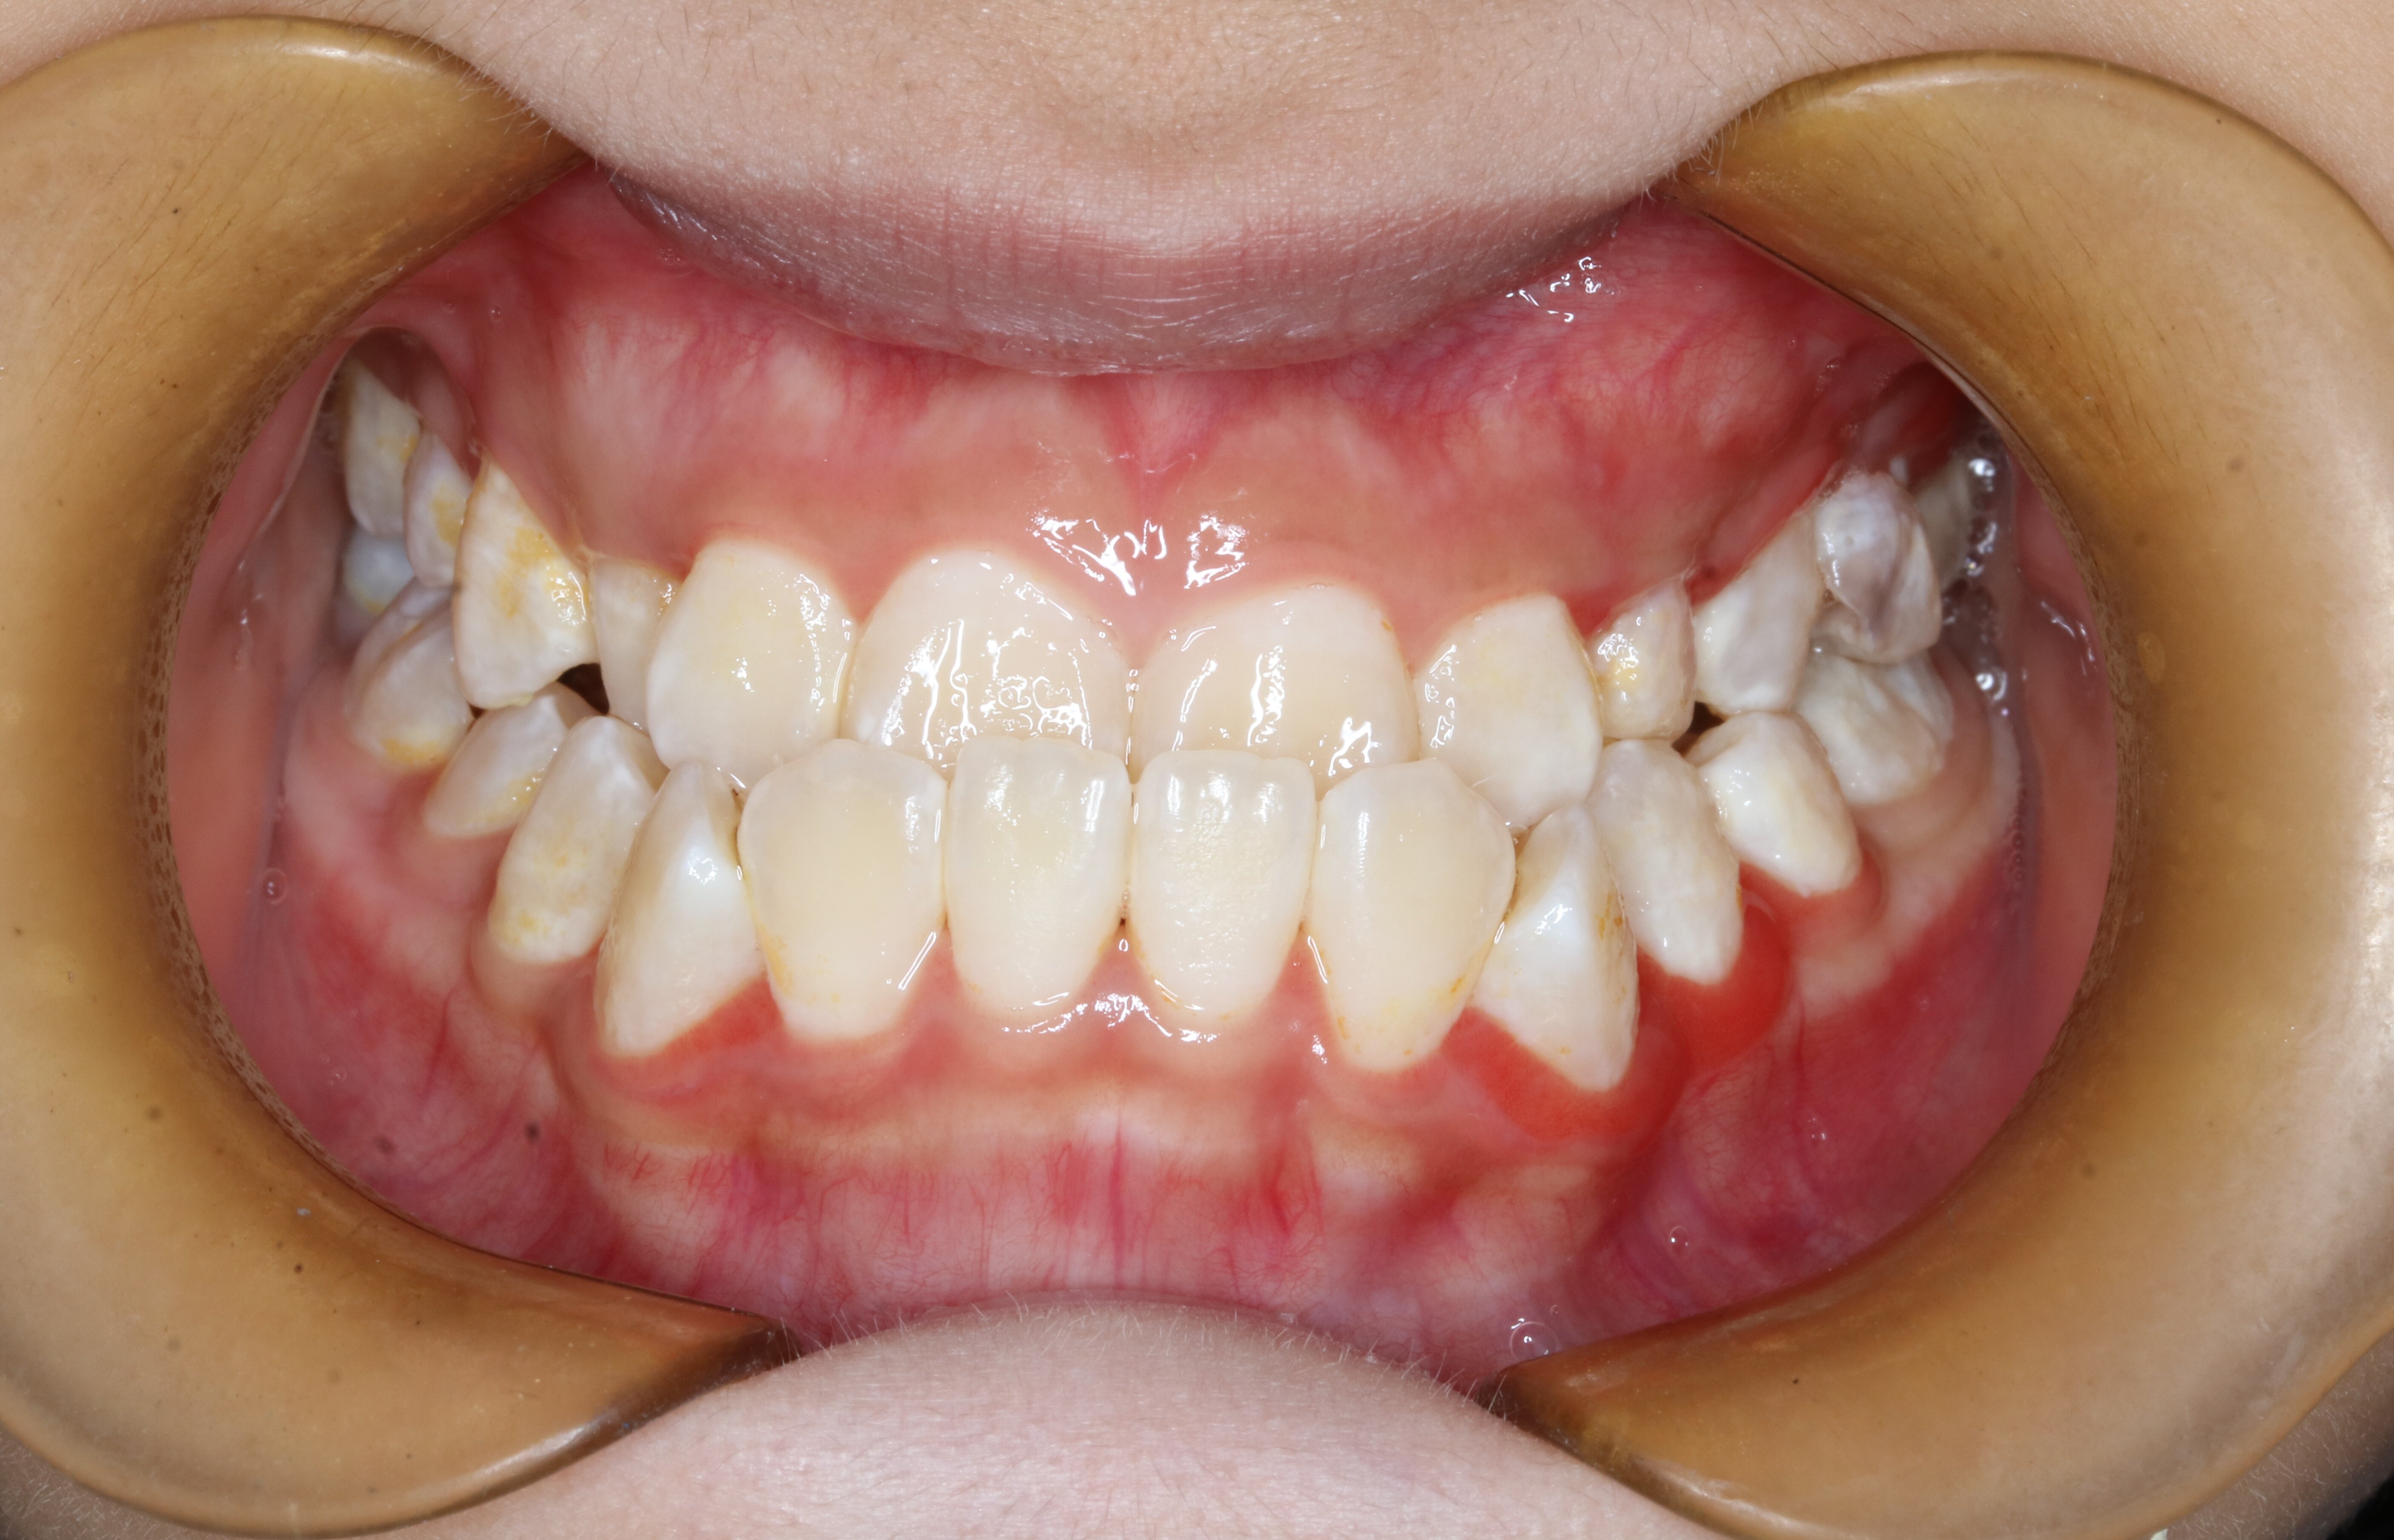

关于儿童牙齿矫正那些事(图1)

反颌

关于儿童牙齿矫正那些事(图2)

偏颌